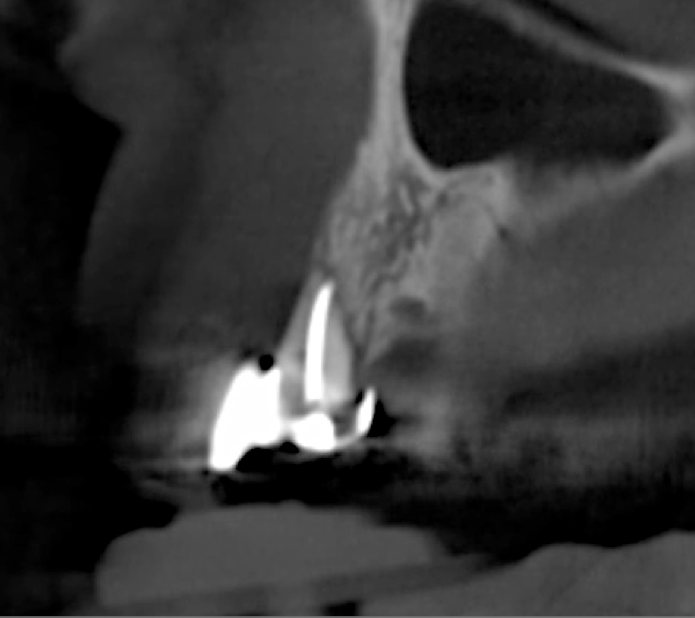

Tomographic images revealed a large tridimensional defect, with vertical and horizontal loss of bone extending to the apical third of teeth Nos. 6 and 8. Additionally, a buccal bone dehiscence was evident on tooth No. 5, and thin labial plates secondary to the orthodontic movement were present in several areas (Figure 3 and Figure 4).

After 3 months of post-orthodontic stabilization, a cone-beam computed tomography scan was taken to re-evaluate the results and plan the future treatment sequence. Tomographic images clearly showed vertical gains in alveolar height, including in the edentulous area corresponding to tooth No. 7 (Figure 10 through Figure 12). The apex of tooth No. 8 was forced-erupted beyond its socket and could be visibly located within the soft tissue.30,33